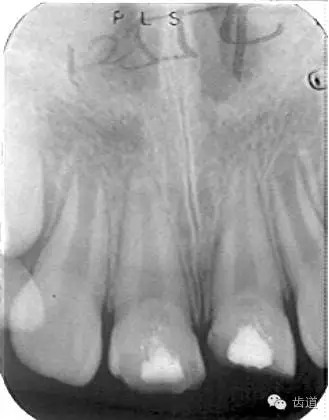

術(shù)后三個(gè)月

術(shù)后六個(gè)月

術(shù)后兩年